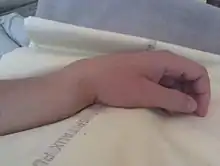

Une fracture de Pouteau-Colles est une rupture osseuse, avec déplacement dorsal, du radius (situé dans l'avant-bras). Elle se caractérise par un déplacement du poignet et donc de la main.

- De profil : aspect en "dos de fourchette" (bascule postérieure du fragment distale du radius).